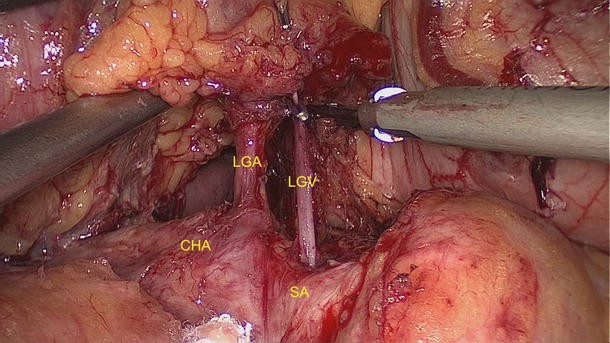

Of the 2,111 gastric cancer patients who underwent radical resection, 6 had the rare anatomic variant of the LGV patients (Figs. 4, 5, 6, 7); the incidence of this finding was about 0.28 %. Its specific drainage pattern differed from that of the normal LGV. In patients with the variant, small vessels from the anterior and posterior walls of the lesser curvature of the stomach drained into the LGV. It lay close to the LGA in the large part of the lesser curvature, descended along the gastropancreatic fold, ran across the dorsal side of the splenic artery and drained into the splenic vein. These vascular anatomies in six patients were documented by the high definition images during laparoscopic-assisted radical gastrectomy.

Fig. 5

figure 5

LGV running across the dorsal side of the splenic artery. LGV left gastric vein, LGA left gastric artery, CHA common hepatic artery, SA splenic artery